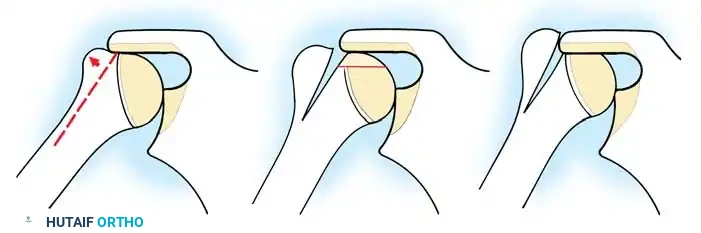

3. Joint Preparation and Decortication

Meticulous preparation of the bony surfaces is paramount to achieving a solid arthrodesis. All articular cartilage must be aggressively removed using a combination of osteotomes, gouges, and high-speed burrs.

The glenoid is decorticated down to bleeding subchondral bone. The humeral head is similarly denuded. To maximize the surface area for fusion, the undersurface of the acromion is decorticated, and a corresponding flat surface is created on the superior aspect of the greater tuberosity.

In some techniques, an intra-articular osteotomy of the humeral head is performed to create a flat, broad cancellous surface that perfectly mates with the decorticated glenoid.